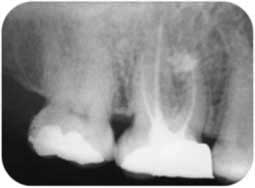

La préparation endodontique se conçoit comme une préparation chimio-mécanique où la mise en forme instrumentale trouve toute sa signification pour influencer la qualité de l’assainissement endodontique. Le plus important réside dans l’obtention d’une conicité régulière et suffisante qui se superpose avec la trajectoire initiale du canal principal, depuis sa partie coronaire jusqu’à la partie apicale (Fig 2a, 2b). Cette conicité, qui permet d’amener les solutions d’irrigation tout au long du canal et en quantités importantes, est obtenue actuellement en utilisant la technique du Crown-Down, aussi appelée préparation corono-apicale.

De nombreux auteurs se sont penchés sur le principe de la mise en forme du tiers apical afin d’éliminer le maximum de bactéries, et il ressort de leurs études qu’il est nécessaire de conserver un diamètre foraminal le plus fin possible et qui correspond au diamètre initial afin d’éviter la propulsion des débris canalaires dans le péri apex et d’assurer l’étanchéité des obturations canalaires qui sont le garant de la cicatrisation apicale (6). Le respect de la longueur du travail est également un facteur clé à privilégier surtout dans les situations où les limites apicales deviennent aléatoires tels les cas de résorptions inflammatoires externes et les apex ouverts.